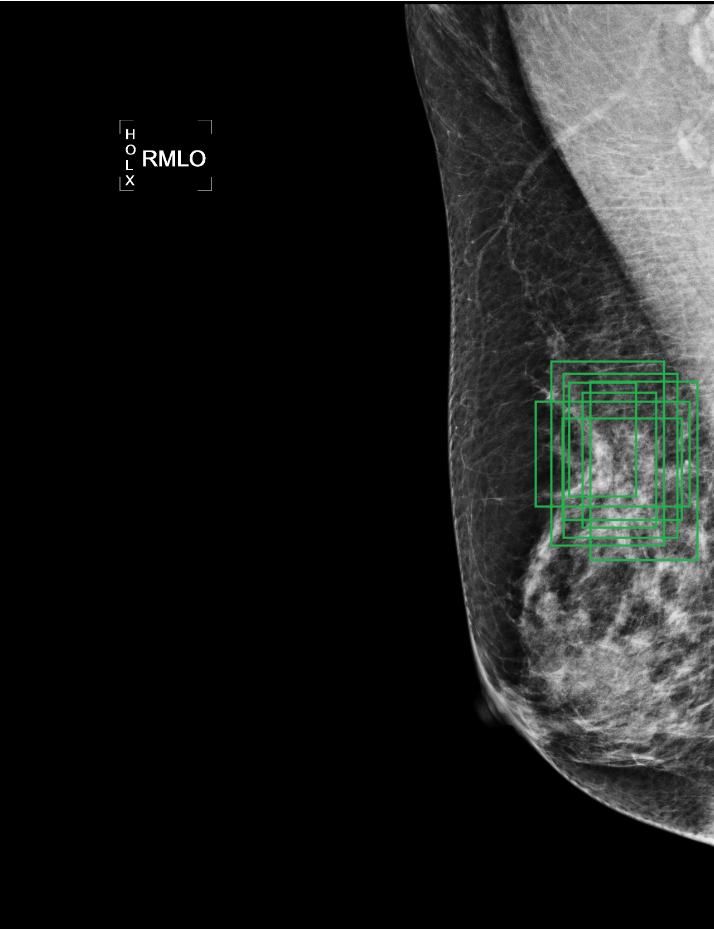

Deep learning object detection algorithm has been widely used in the task of classifying or detecting objects of natural images [3] and [8], and are receiving more and more attentions on its usage in medical image analysis. However, current object detection tasks are all based on the data annotated with object classes and their bounding boxes, those images which are not considered during labeling may contain regions or objects that are similar to the target ones, and may be misclassified in the testing stage. This phenomenon is critical in medical image analysis. For example, as shown in Fig.(1), a healthy mammography may contain benign or normal regions whose features are very similar to a malignant lesion. On the other hand, when doctors perform labeling, they usually search for medical records of patients that are diagnosed as cancer first, and only selected samples are labeled and used for training. As a result, those healthy samples that contain suspected malignant regions are likely to be classified as malignant.

In the following, we define a mammography with malignant lesions as a positive image, and those malignant lesions as positive targets or targets. All the other mammography are defined as negative images, including those images contain benign or normal regions that are highly suspect to be malignant(as shown in Fig.(1)). And without loss of generality, we called those highly suspected malignant regions as suspected target regions. Within the datasets we used, all the positive targets are annotated with bounding boxes to indicate their precise locations and all the negative images do not have any annotation.